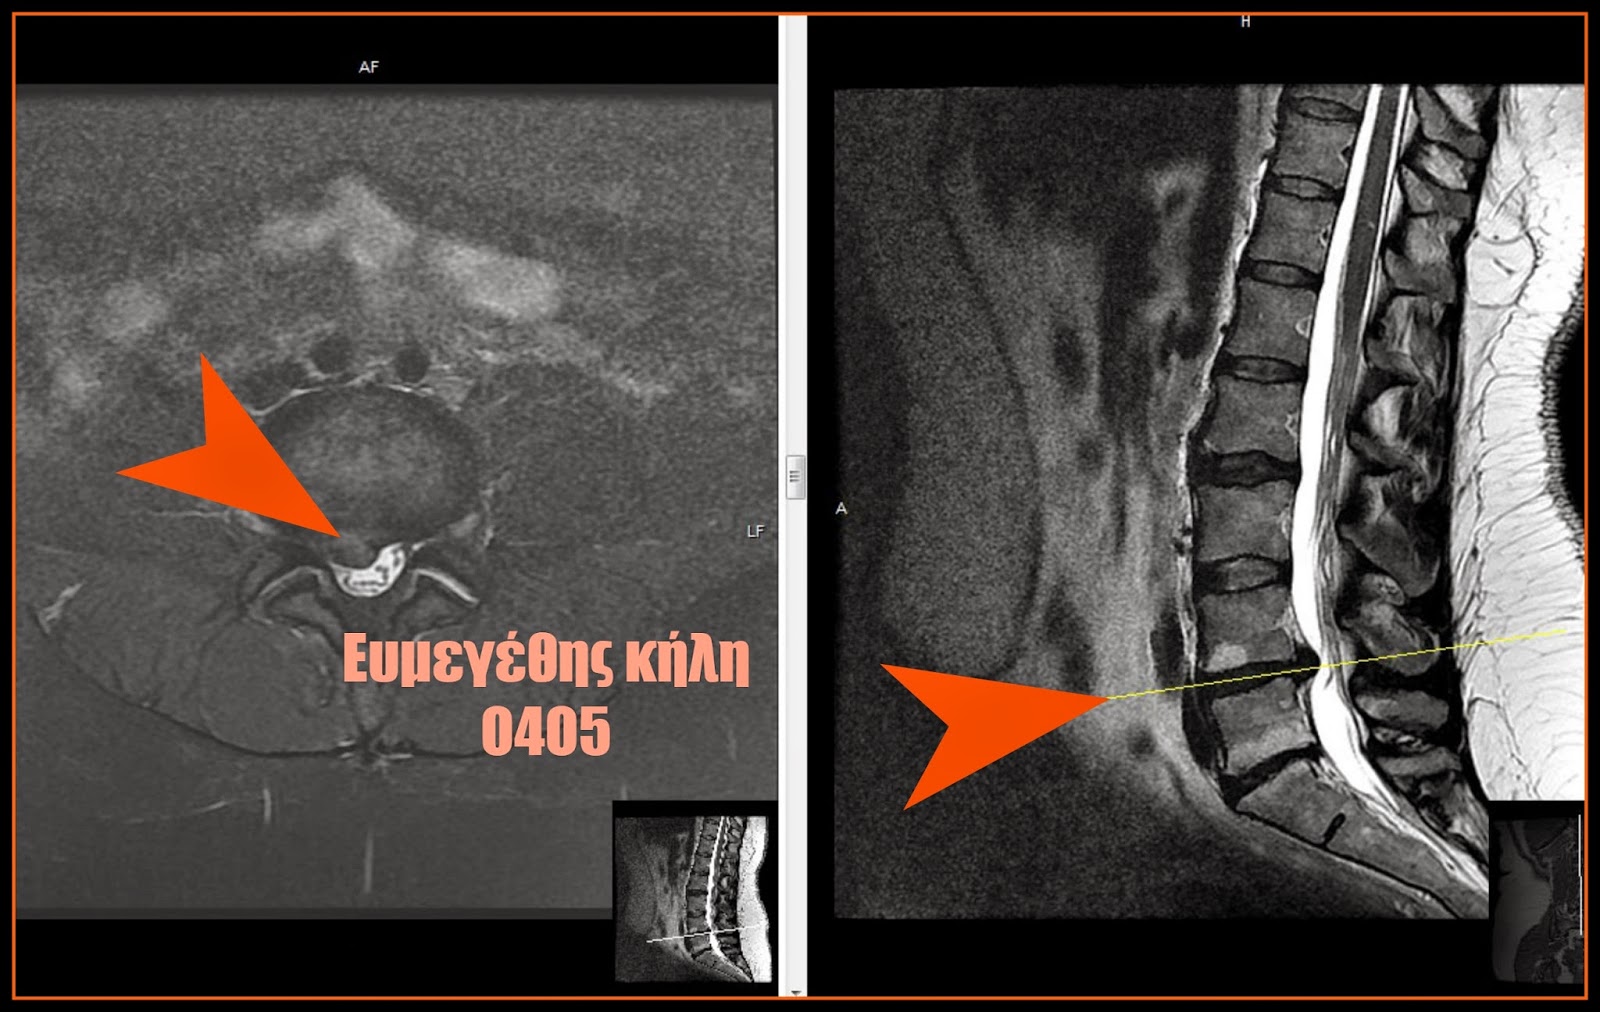

J Neurosurg Spine 42:727–736, 2025 This multicenter retrospective study of

75 patients found that prompt surgical intervention for unilateral painful